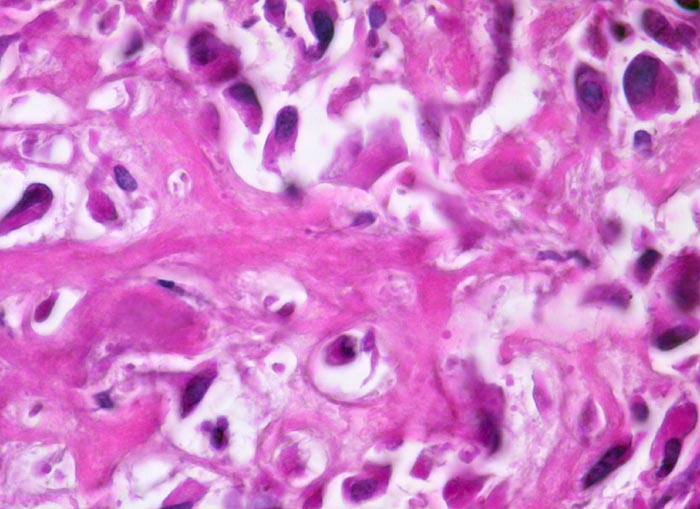

Morphologische Merkmale:

• Tibiametaphyse mit angrenzendem Weichteilgewebe.

• Das Sarkom infiltriert diffus den spongiösen Knochen der Diaphyse und hat präexistente Knochenbälkchen verdrängt.

• Der Tumor hat die Korticalis destruiert und infiltriert die angrenzende Skelettmuskulatur.

• Der Tumor besteht aus neugebildetem bereits verkalktem Knochen oder einem Netzwerk von primitiven Osteoidtrabekeln. Entlang oder innerhalb der Osteoidtrabekel lokalisierte polymorphe Tumorzellen mit ausgeprägten Kernatypien und zahlreichen Mitosen. Leicht verwaschene Kernstrukturen als Folge der Gewebsentkalkung.